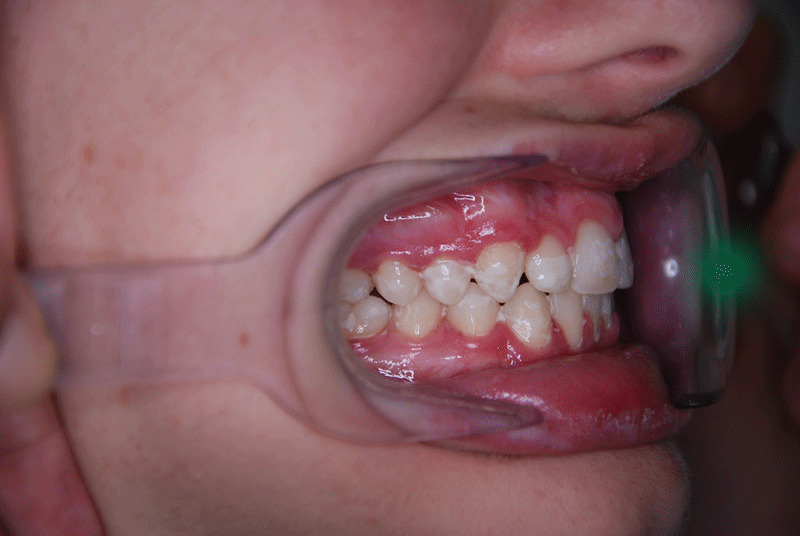

Deepbite

How do you fix a deep bite in a child?

In children, deep bite is corrected with interceptive orthodontics. To avoid excessive wear, it is ideal to start treatment between approximately five and nine years of age.  Fixed orthodontic treatment is performed to correct it during adolescence, since at that age it is too late for an interceptive treatment option.